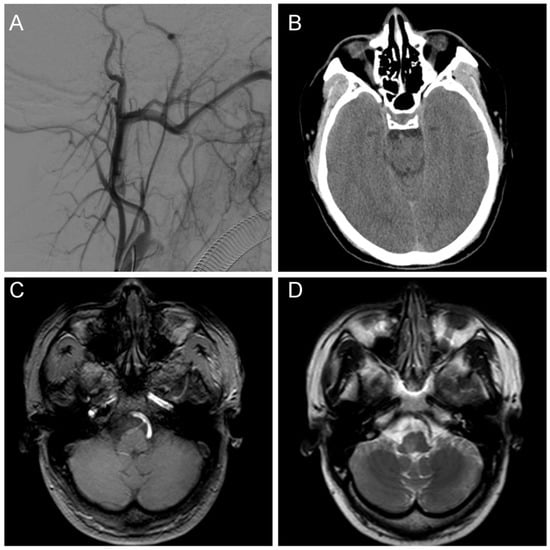

We ruled out the possibility of an intracranial hemorrhagic lesion, which is often associated with increased intracranial pressure, severe headache, or loss of consciousness [6,7,8]. To further clarify the diagnosis, we performed a digital subtraction angiography (DSA) examination, which showed that our preoperative diagnosis was inaccurate and the mass lesion was not caused by a tumor. DSA examinations revealed CCJAVFs, where the right ascending pharyngeal artery acted as the donor artery, and the spinal veins and the occipital cortical veins acted as the drainage veins (Figure 2A–C). The treatment modality should be decided by the anatomical structure and the position of AVF, for which the operation or the intravascular intervention was suitable. The DSA examination suggested that a craniotomy would be unnecessary and that this patient only required management of the arteriovenous fistula. Based on these preoperative findings, an endovascular intervention was performed. A 6F guide sheath was placed through a puncture in the right femoral artery, and a 6F guiding catheter was applied for imaging. The 6F guide catheter was placed at the beginning of the right external carotid artery with the assistance of a guidewire under the roadmap. The contrast media determined that there was no spasm of the vessel. A microcatheter was placed into the site close to the fistula under the road map for embolization, and a spring coil was placed in the superior trunk of the right ascending pharyngeal artery to reduce blood flow and further thrombotic occlusion (Figure 3A,B). The angiogram showed a significant decrease in the blood flow in the superior trunk of the ascending pharyngeal artery. Then, an Onyx biologic gel was injected slowly and intermittently into the upper and lower trunks of the ascending pharyngeal artery through the microcatheter (Figure 3C,D). The diffusion and regurgitation of the Onyx biologic gel were repeatedly observed via microcatheter imaging until the branch at the fistula was completely embolized. The angiogram showed a complete non-visualization of the supply artery and drainage vein, and all intracranial branches were present. Five days after surgery, the DSA analysis showed a complete embolization of the fistula (Figure 4A). The CT examinations showed a lamellar, slightly hypointense shadow in the brainstem, without hemorrhage or ischemia (Figure 4B). The MRI examinations showed lamellar, slightly long T1 and slightly long T2 signals in the brainstem, with a maximum cross-section of about 10 mm × 8 mm. The brainstem mass lesion after treatment was reduced when compared to that before treatment (Figure 4C,D). It is important to note that embolization may pose an additional risk. Dimethyl sulfoxide injection is required prior to embolization and may have potential neurotoxicity. Access vascular injury may occur during embolization. If the biogel enters a vessel other than the lesion site, it may cause cerebral infarction. During embolization, hemodynamic changes also require attention. In fact, immediately after the patient’s surgery was completed, we transferred the patient to the ICU for detailed monitoring as well as an assessment of the patient’s status. After 7 days of monitoring, we confirmed that the patient had no complications and then transferred him to the general ward. The patient recovered well after the operation, and his headaches and hoarseness decreased. He was discharged with a Karnofsky score of 90.

Figure 4.

Postoperative examination. (A) A postoperative DSA examination indicated complete fistula occlusion; (B) A CT examination indicated no hemorrhage and ischemia at the site of the lesion; (C) The T1 sequence of MRI showed a slightly long signal area in the brainstem without abnormal postoperative injuries; (D) The T2 sequence of MRI showed a slightly long signal area in the brainstem with a normal cranial structure.